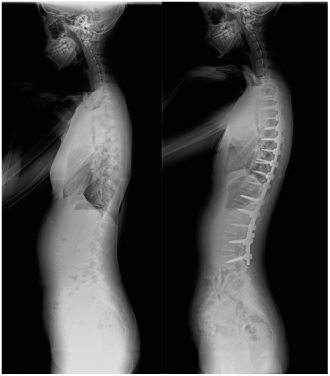

側弯症の手術方法

側弯症の手術方法は、後方矯正固定術(背中から手術する)、前方矯正固定術(お腹側から手術をする)に大別されますが、現在は後方矯正固定術という術式が主流となっています。

後方矯正固定術は、背中の正中部分(真ん中)を切開し、最も傾いている椎体から逆向きに最も傾いている椎体の間にかけて、背骨が見えるように背骨の周囲についている筋肉をはがします。

その後、それぞれの背骨の左右にスクリューを2本ずつ挿入し、それらをロッ ドと呼ばれるチタン合金やコバルトクロム合金のバーで連結することで側弯を 矯正します。各椎体の間にある関節(椎間関節)に、局所の骨や人工骨を移植した後、出血をはじめとする合併症がないことを確認して、傷を閉じます。

術後は、痛みに合わせて5〜7日目から歩いてもらい、傷が塞がって大丈夫と判断された後に退院となります。一般的な入院期間は、2週間程度です。側弯症手術にとってもっとも大事なことは、矯正された脊椎がその形で骨癒合することです。自分の骨を移植するのはこのためですが、骨癒合には術後数ヵ月の時間が必要です。よって術後には数ヵ月運動ができなくなります。その後は外来で経過観察しながら、徐々に運動を開始して頂きます。